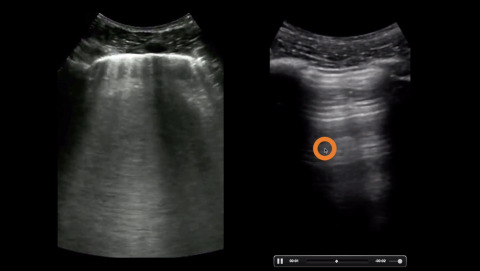

Approach to the Ultrasound of Pneumothorax

Dr. Avila reviews the ultrasound findings in pneumothorax.